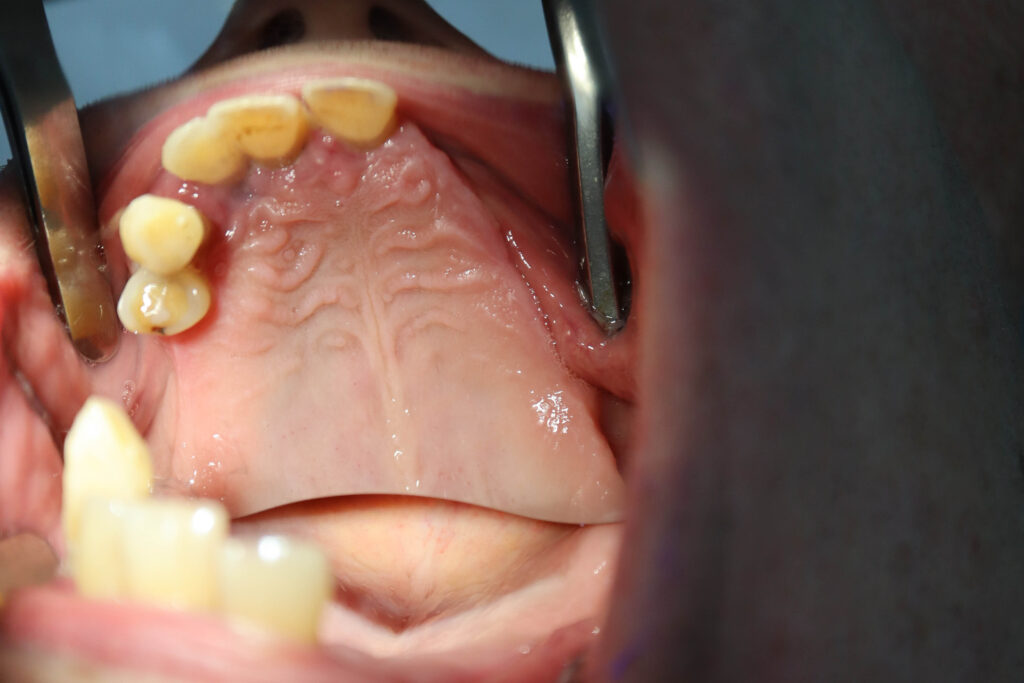

процесс имплантации

Это фото может содержать тяжелый для восприятия контент

На верхней челюсти была проведена комплексная имплантация по системе All-on-5,

установлены 3 имплантата Megagen AnyOne и 2 скуловых имплантата NeoDent.

На нижней челюсти были установлены 4 имплантата Megagen AnyOne.